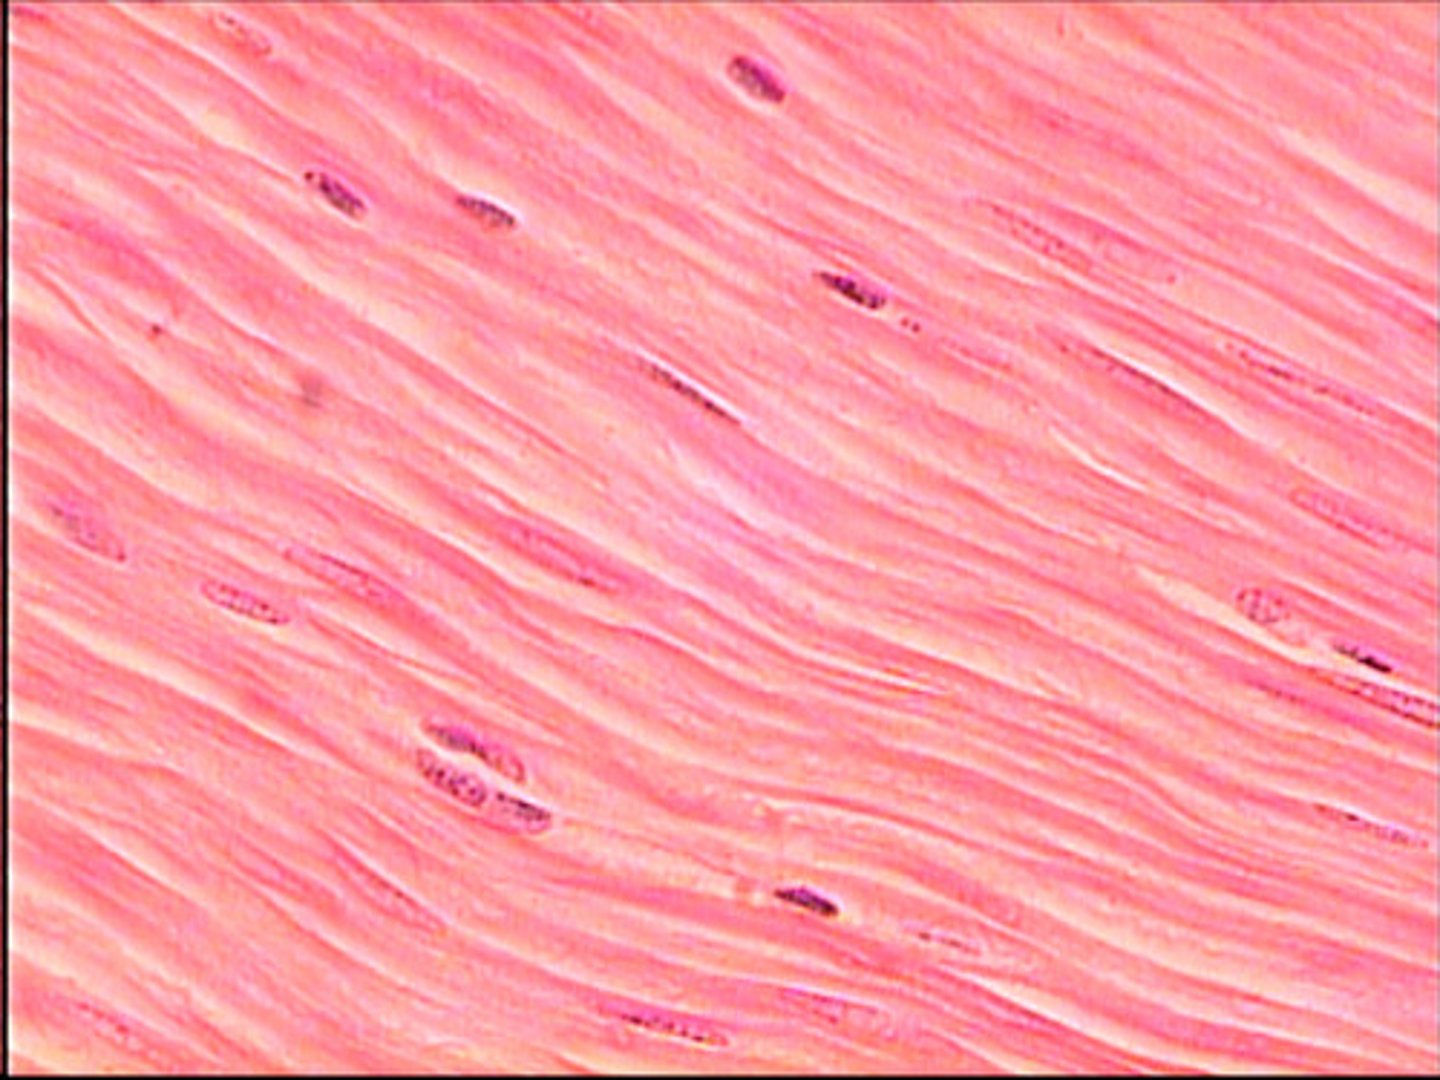

smooth muscle is

a. striated

b. un-striated

smooth muscle

smooth muscle is under ______ control

involuntary

smooth muscle is _____-nucleated

mono-nucleated (1 nucleus)